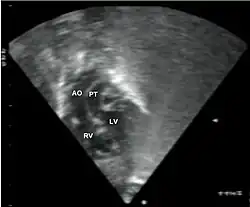

Additional images